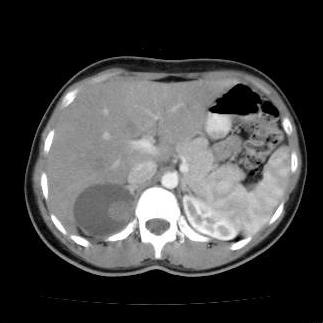

Nang tuyến thượng thận (Adrenal cyst)

Adenoma tuyến thượng thận (Adrenal adenoma)

U tủy mỡ thượng thận (Adrenal myelolipoma)

U tủy thượng thận (Pheochromocytoma)